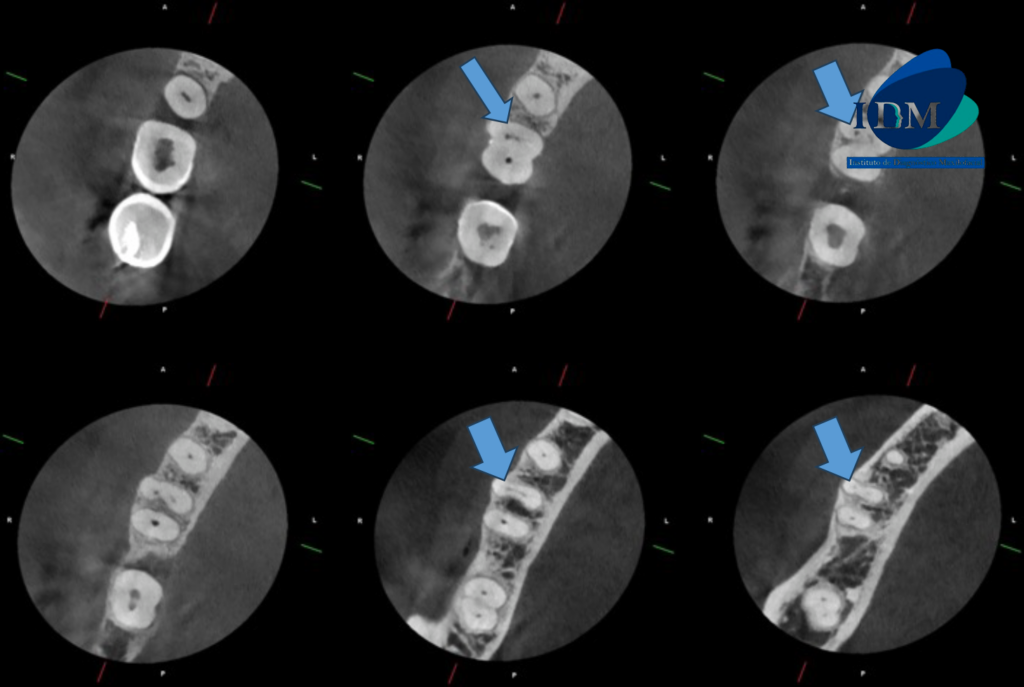

CORTES AXIALES

Sin embargo respecto a la conformación de los conductos pulpares podemos observar que la raíz mesial presenta un conducto colateral hacia palatino que a su vez confluye con el conducto pulpar principal para nuevamente separarse, todo esto a nivel del tercio apical.